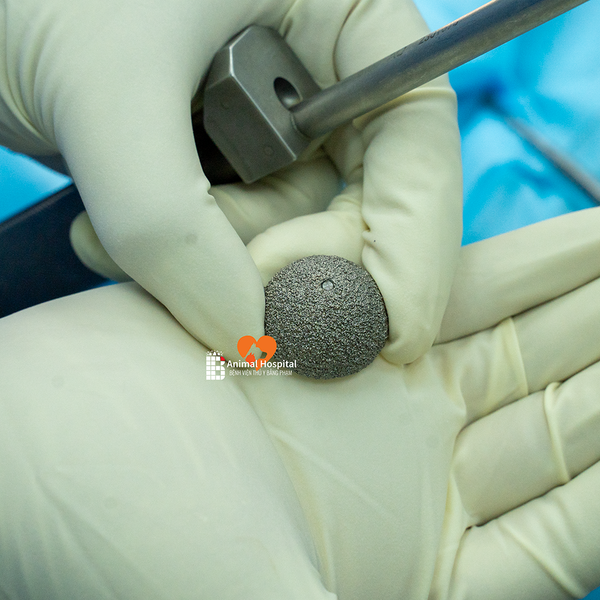

⚙️ Cấu hình sử dụng | Implant Configuration

- Chỏm đùi: PEEK 20mm

- Cup acetabulum: Titan không xi măng 25mm

- Thân femur: Không xi măng size #8

- Cổ xương: Size 0

- Ốc bên: 22mm cố định cup